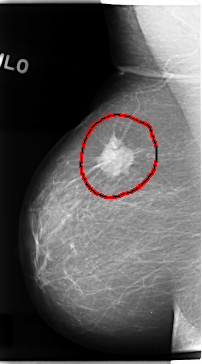

C_0121_1.RIGHT_MLO

RIGHT_MLO LINES 4728 PIXELS_PER_LINE 2624 BITS_PER_PIXEL 12 RESOLUTION 50 OVERLAY

FILE: C_0121_1.RIGHT_MLO.OVERLAY

TOTAL_ABNORMALITIES 1

ABNORMALITY 1

LESION_TYPE MASS SHAPE IRREGULAR MARGINS SPICULATED

ASSESSMENT 5

SUBTLETY 5

PATHOLOGY MALIGNANT

TOTAL_OUTLINES 1

BOUNDARY